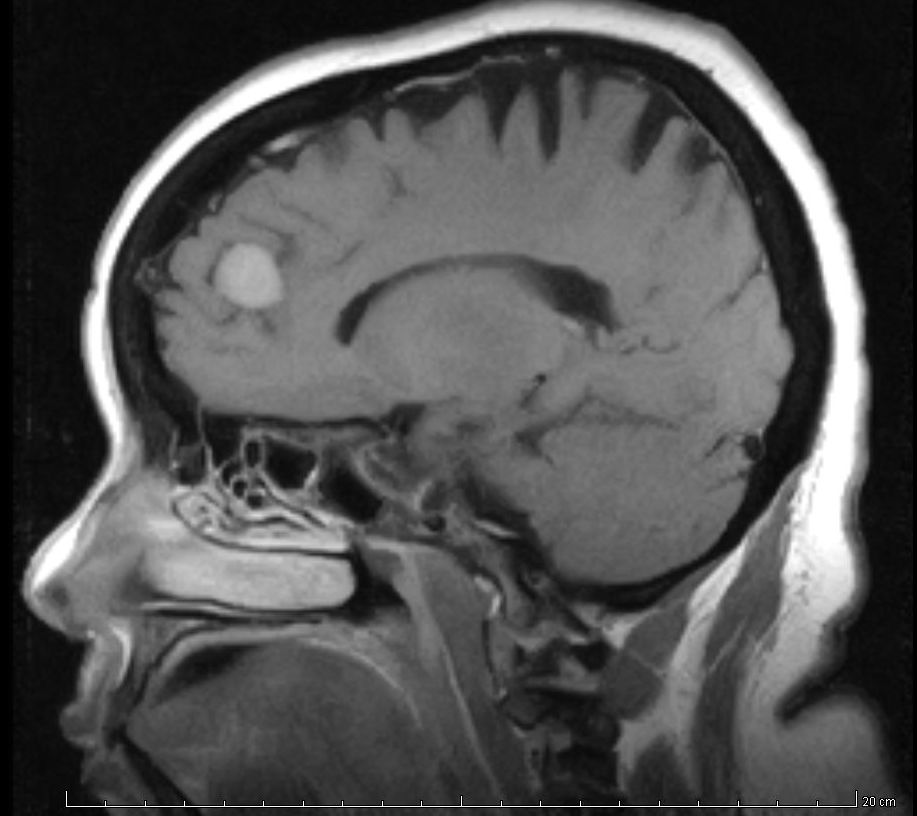

Aten Primaria. 29 de septiembre de 2018. El sobrediagnóstico del cáncer es la detección de cánceres asintomáticos que no crecen o que están creciendo con tal lentitud que nunca habrían causado problemas médicos en el paciente en el transcurso de su vida. Aunque el sobrediagnóstico puede darse en cualquier enfermedad, es más relevante en el caso del cáncer.